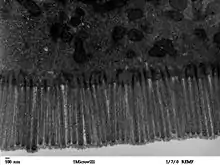

The mucosal layer consists of a epithelial layer, and its underlying supportive tissue, the Lamina Propria. It is separated from the submucosal layer by the Muscularis Mucosa. The epithelial layer varies from section to section of the gut. In the oesophagus it is a non-cornified stratified squamous epithelium; in the stomach it is mainly mucosal cells; the small intestine and large intestine are characterized by absorptive cells, with many mucous producing goblet cells. In the absorptive sections of the intestine, the surface are for absorption is greatly increased by finger-like projections into the lumen called villi, and the absorptive cells themselves also have small projections of microvilli, giving them the appearence of a brush border when viewed with a light microscope.

The surface for absorption is increased in many ways: the mucosa of the small intestine is thrown into folds called rugae; the mucosa itself has numerous finger-like projections called villi, and the epithelial cells are also covered with numerous projections called microvilli. The microvilli give the appearance of a 'brush' on light microscopy; hence the term brush border. The following illustration shows the anatomy of a villi:

Mucous is secreted by numerous goblet cells; other cells are specialized for absorption and are known as absorptive cells. In the base of the crypts are numerous secretory cells which secrete the digestive enzymes of the small intestine. Some of the crypts penetrate into the submucosal layer, forming digestive glands which will communicate with the mucosa via a secretory duct.

Epithelial cells have a lifetime of 5–7 days. New cells are continuously being generated in the crypts, and migrate up the sides of the villi. These cells differentiate into either goblet cells (10–25%) or absorptive cells. Old cells are shed from the tips of the villi, migrating upwards and forming new villi.